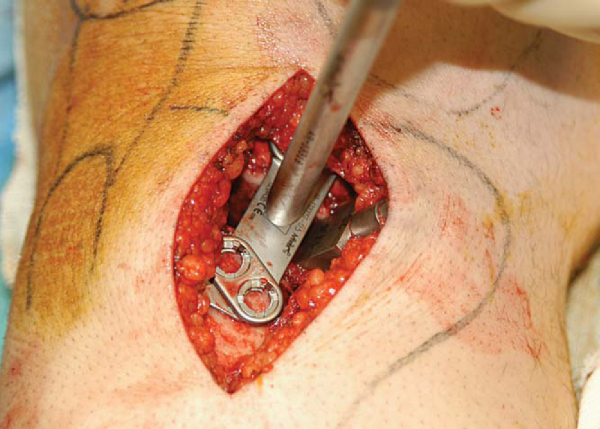

The medial aspect of the osteotomy can be opened further for larger corrections by inserting the screw jack into the osteotomy and gradually advancing the screw to apply a controlled opening force (

Fig. 58-8

). A graduated Puddu wedge is then inserted at the same angle as the osteotomy, creating the exact wedge height as had been calculated preoperatively. The graduated wedge should be advanced slowly (5 mm/min) to allow gradual opening of the osteotomy (

Fig. 58-9

). A wedged Puddu plate of the same size is then inserted (

Fig. 58-10